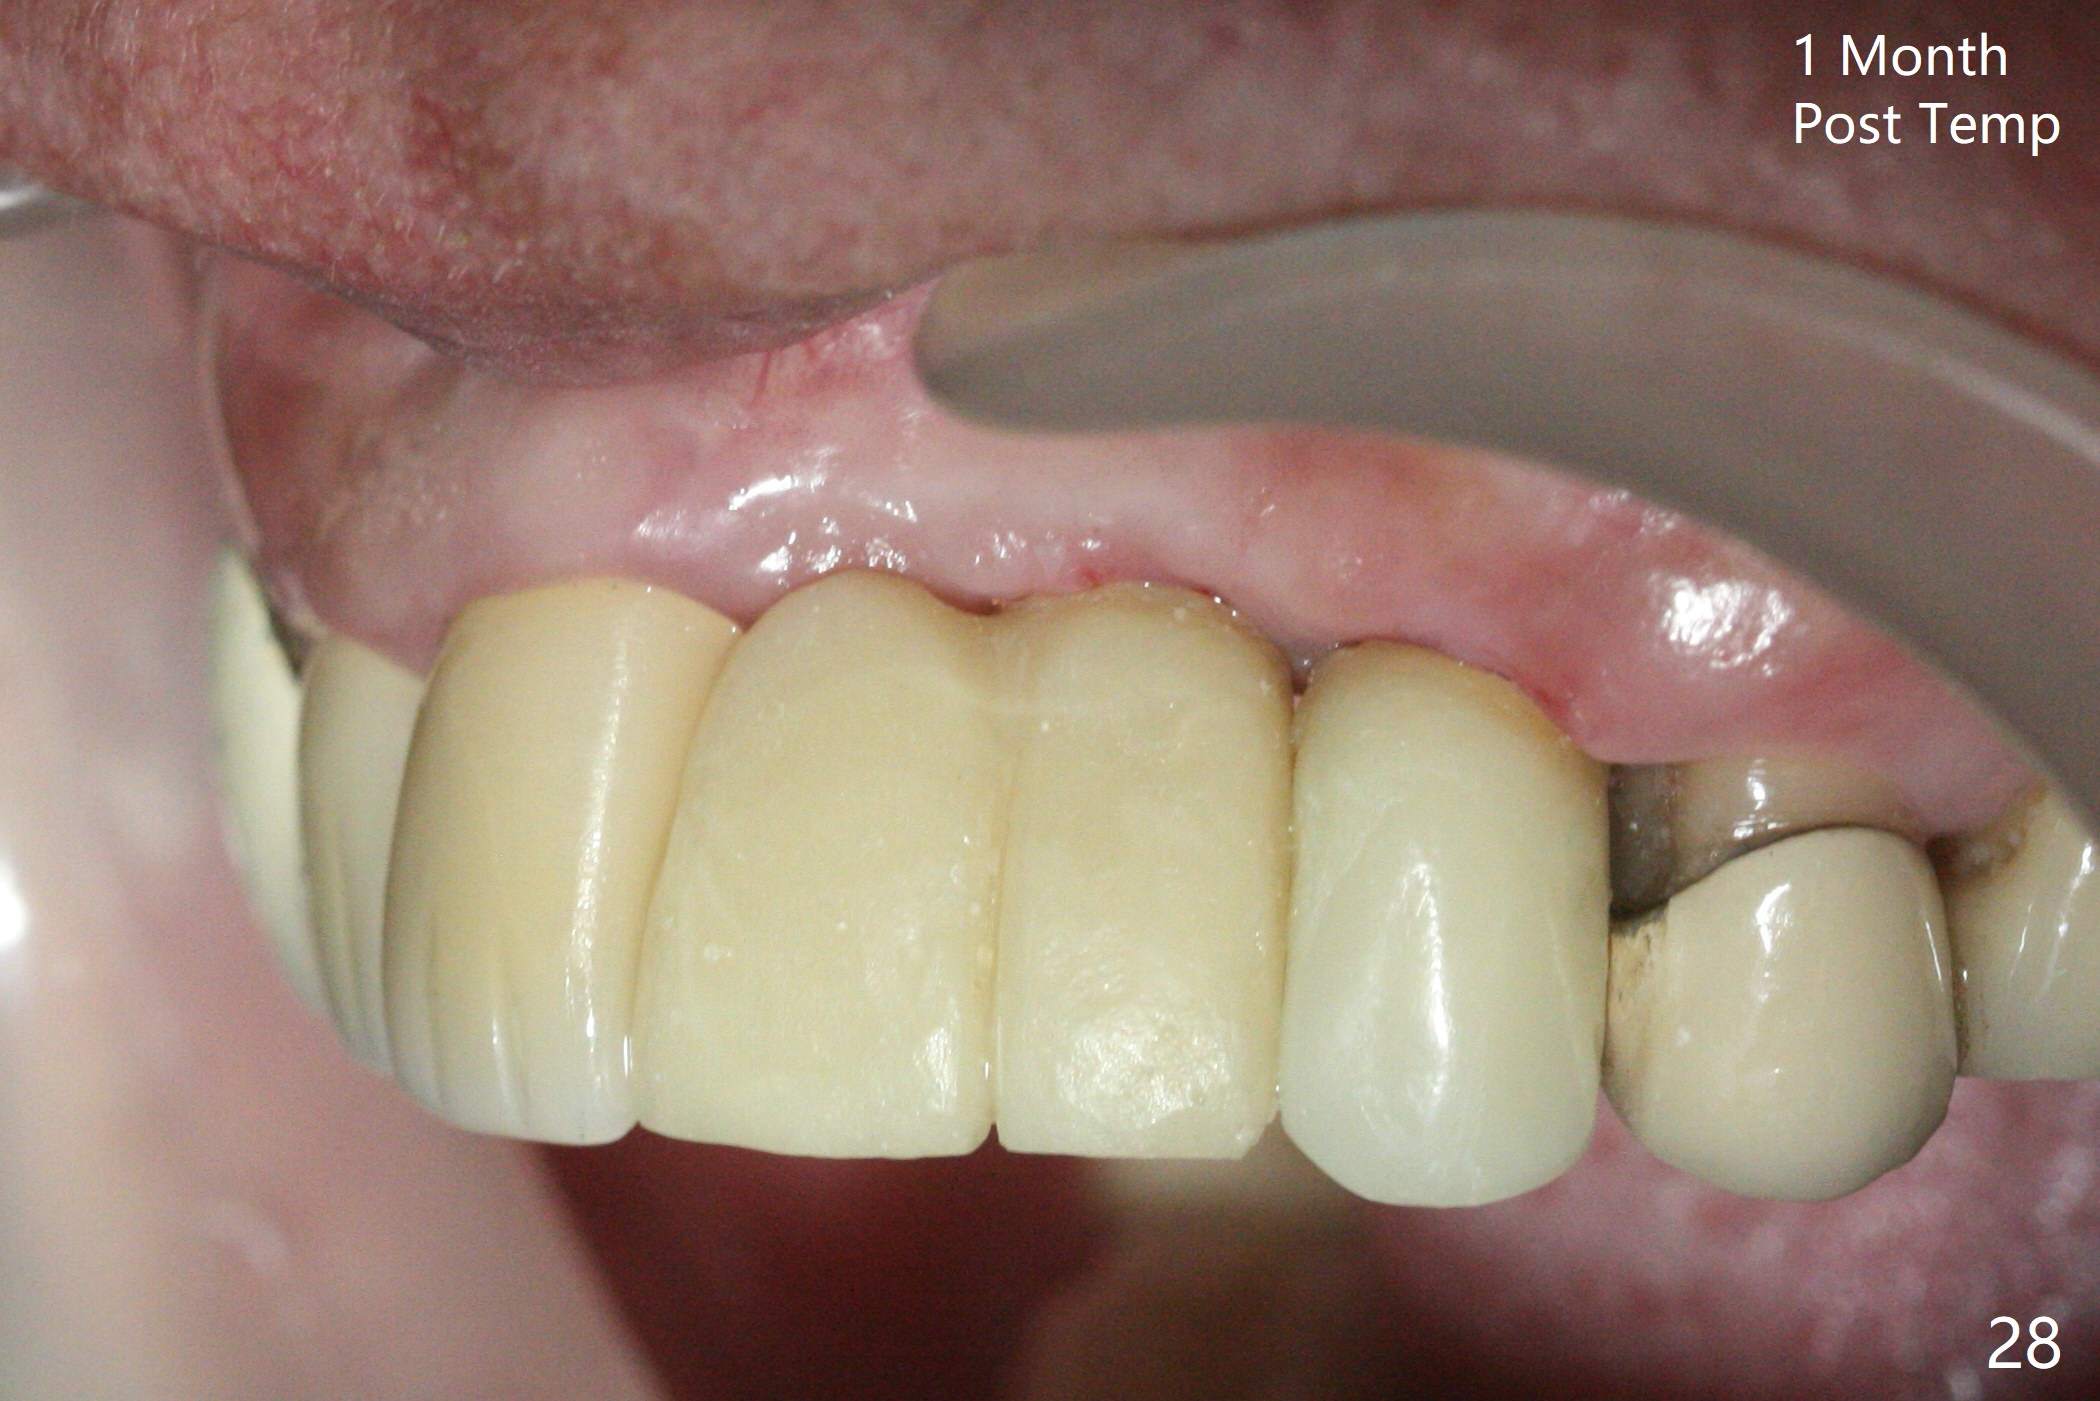

The mesiobuccal margin at #8 is redefined 4 weeks postop (Fig.14) so that the cervical end of the temporary crown is able to move mesially (Fig.13). The most coronal portion of the bone graft at #11 begins to be detached (*). The mesial portion of the abutment at #10 will be removed (curved white line) in the following week. After removing the most coronal portion of detaching bone graft at #11, acrylic is added to form a concave pontic (Fig.15 ^). With removal of the mesial portion of the abutment at #10, the retainer is moved distal (>). Pontics form at UL1 and 3 two months postop (Fig.16 *), while there is buccal atrophy at UL1,2 (Fig.17). 术后3个月植牙区牙龈形态良好(图十八),即将暴露,放置愈合基台。图十九是在右上1根管治疗时(基台放置后五天)拍摄。左上3术后3个月3个星期,1,2唇侧塌陷(图二十)。叶状植体处牙槽嵴往根尖萎缩(图二十一:^)。尽管做了松弛切口,放入事先预备的粘性骨粉后,几乎没有空间放置结缔组织移植物,恰好还没有取。放置PRF膜后,使用4-0 Monoglyc缝线缝合。牙龈似乎冠方移位(图二十二:箭头)。植骨后,唇侧仿佛饱满多了(图二十三:*)。骨粉放置于左上1,2唇侧和牙槽嵴(图二十四:*,与之前(图十九)对比)。后者有助于牙龈冠方移位,而前者有助于增加唇侧饱满度。植骨术后两周唇侧仍饱满(图二十五,六)。植骨后四个月牙冠粘固,两个月后,病人抱怨10号牙左右食物坎塞(图二十七),9/10牙冠撤除,10基台边缘加深,重做临时牙冠,同时增加9凹陷(pontic)。一个月后,9/10临时牙冠修整两次,11永久性牙冠撤除,也制备临时牙冠,外形明显改善(图二十八)。